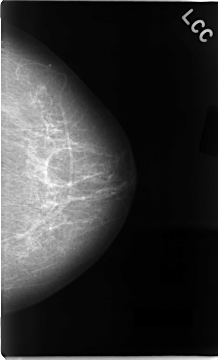

Digital Database for Screening Mammography

Volume: cancer_02 Case: C-0022-1

C_0022_1.LEFT_CC

LEFT_CC LINES 4672 PIXELS_PER_LINE 2824 BITS_PER_PIXEL 12 RESOLUTION 50 NON_OVERLAY

LEFT_MLO LINES 4696 PIXELS_PER_LINE 2792 BITS_PER_PIXEL 12 RESOLUTION 50 NON_OVERLAY